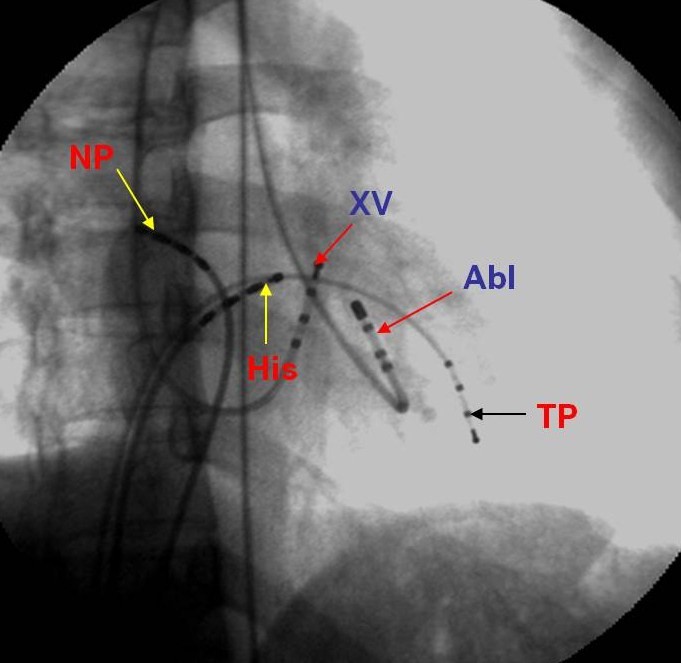

Hình 7: Vị trí các ống thông trên hình ảnh X quang trong triệt đốt đường dẫn truyền phụ: NP: điện cực cùng cao nhĩ phải, His: điện cực vị trí bó His, XV: điện cực xoang vành, TP: điện cực mỏm thất phải, Abl: điện cực triệt đốt được đưa vào thất trái ngược chiều qua van động mạch chủ và cắm vào vòng van hai lá nơi có đường dẫn truyền phụ nhĩ-thất đi qua.

Hình 11: Vị trí các ống thông trên hình ảnh X quang trong triệt đốt đường chậm ở tư thế nghiêng trái 30 độ (trái) và nghiêng phải 30 độ (phải): NP: điện cực cùng cao nhĩ phải, His: điện cực vị trí bó His, XV: điện cực xoang vành, TP: điện cực mỏm thất phải, Abl: điện cực triệt đốt được đưa vào vùng đáy của tam giác Koch, dưới vị trí điện cực bó His khoảng 2 cm và ngang mức với lỗ xoang vành.